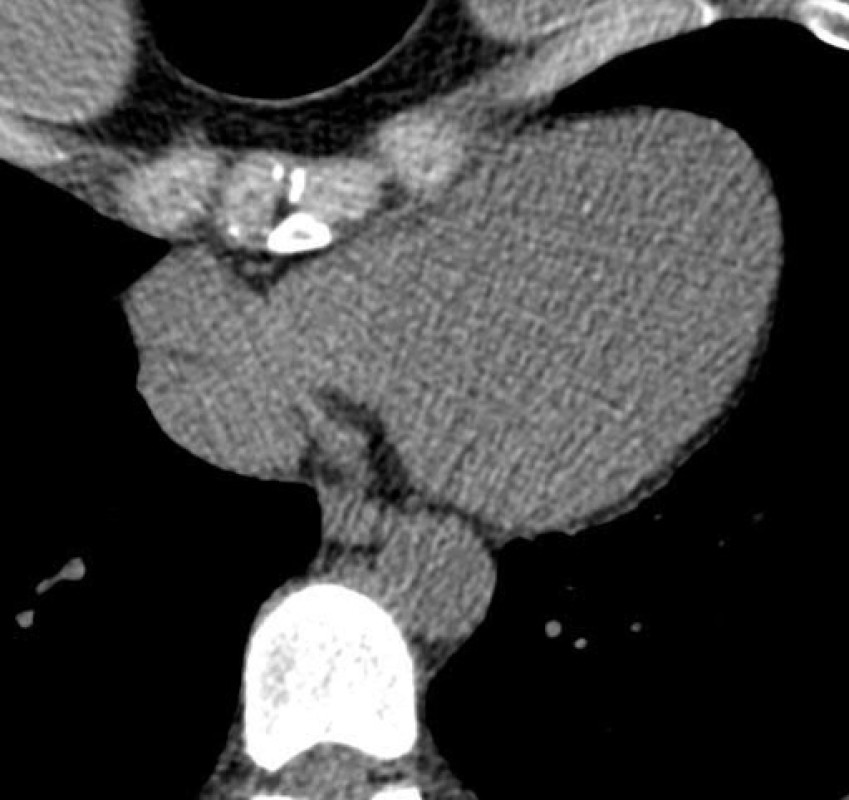

Hello. My name is Jennifer Aldridge and have recently found out that I will need surgery to give my heart and lungs more space. I am so scared. It will require me to be off 4-6 months from work as i have heavy lifting involved in my work. This surgery will allow me to breath as I should and heart compression released. My spine and sternum almost touch. I need to pay for some of surgery costs and living costs while im off from work. I have already exhausted all sick and annual leave and savings. Please help if you can. ❤️🙏